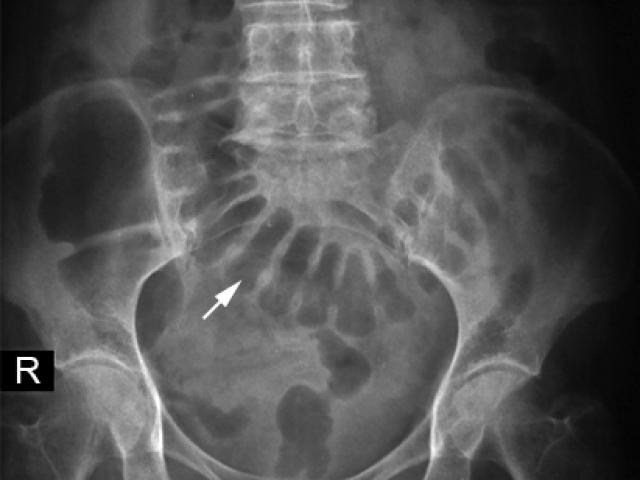

Qua thăm khám và làm các chỉ định cận lâm sàng cho thấy có hình ảnh tắc ruột và các quai ruột giãn to.